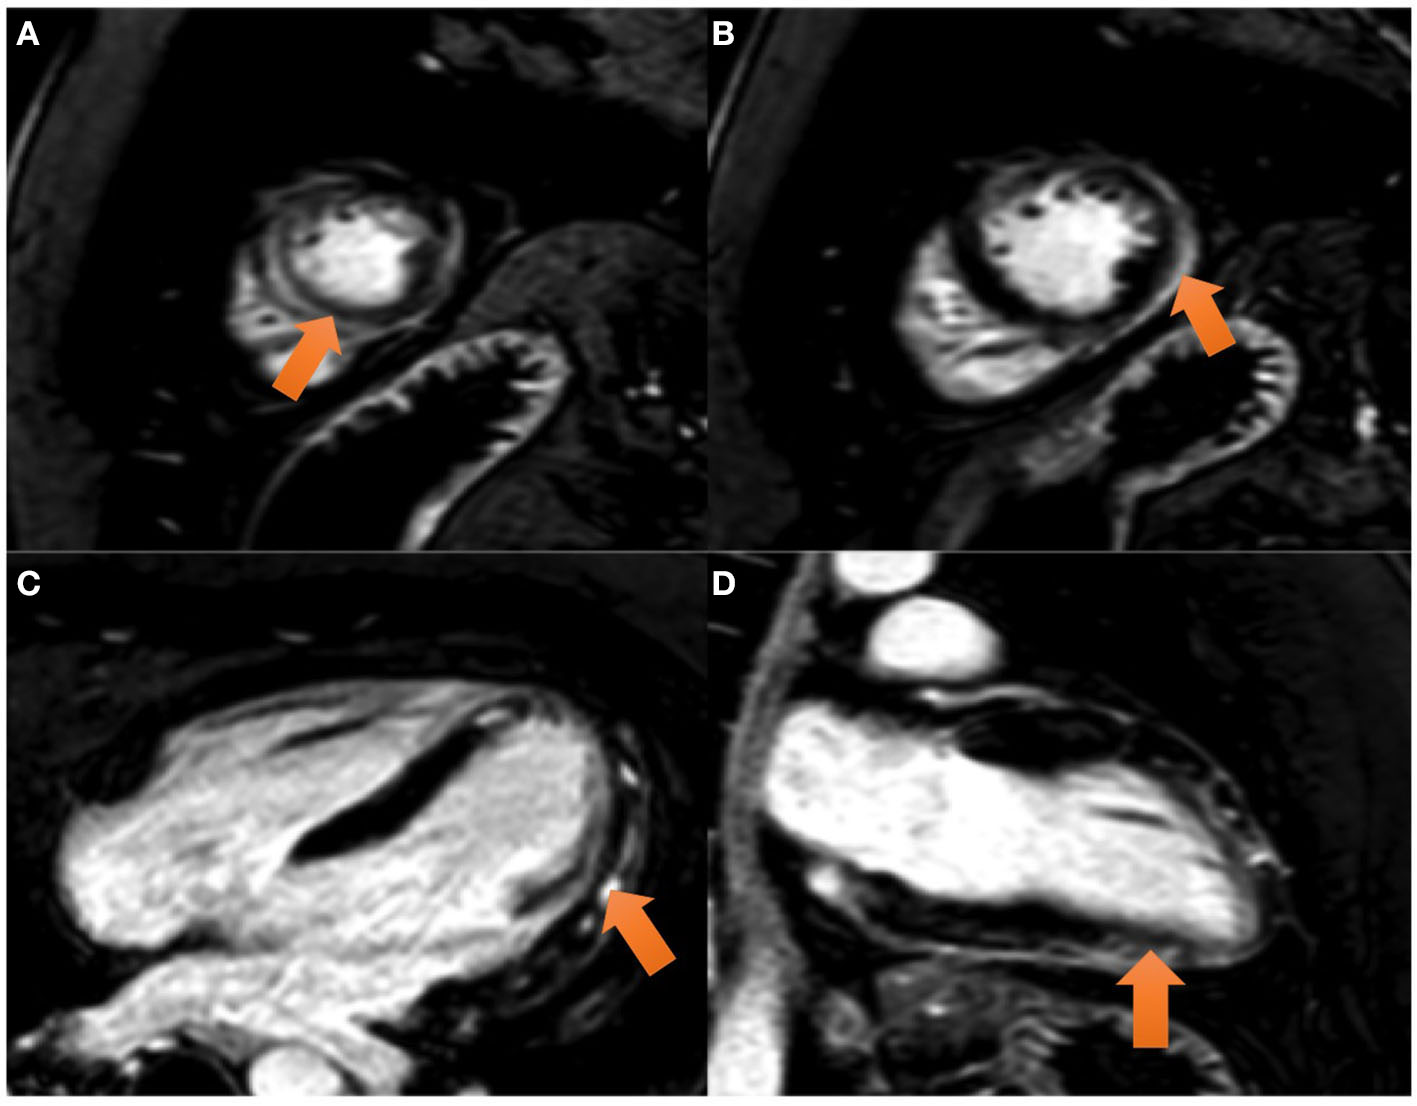

Figure 2

CMR images: the balanced FFE (fast field echo) sequences acquired along the short axis (A, B) and two chamber (C) and four chamber (D) views demonstrate myocardial late gadolinium enhancement with epicardial predominance in the lateral and inferior wall and mesocardial predominance in the septum and anterior wall (view arrows).

Cardiac Magnetic Resonance (CMR) performed on day 6 showed a preserved left ejection fraction (56%) with no regional wall abnormalities. An increased myocardial and pericardial signal intensity on the T2 STIR sequence was suggestive of edema (Figure 2A). On the T1 mapping, an average native T1 of 1,160 ms was observed, and on the T2 mapping, an average T2 of 60 ms was observed. In addition, the quantitative assessment of the cardiac ECV (extracellular volume) was 35%. The T1 and T2 mapping values were measured on a 1.5 Tesla MR Philips machine within a single breath-hold using a modified Look-Locker with inversion recovery (MOLLI) and gradient and spin echo (Gra-SE) sequences, respectively. Normal native myocardial T1 values lie between 1,025 and 1,075 ms, whereas T2 values lie between 50 and 57 ms (internally validated). A color-coded image of T2 mapping (Figure 2B), native T1 (Figure 2C), and enhanced T1 mapping (Figure 2D) were also performed. Late gadolinium enhancement (LGE) images, obtained by using a balanced fast field echo (FFE) sequence, showed subepicardial and mesocardial enhancement of the myocardium and mild signs of pericarditis, which were considered consistent with acute myopericarditis (Figures 3A–D). The patient met all modified Lake Louise criteria for myocarditis: T2 criteria (myocardial edema shown on a T2 STIR sequence and T2 mapping) and T1 criteria (non-ischemic myocardial injury shown on an LGE sequence and T1 mapping). Signs of mild pericarditis were also exhibited.